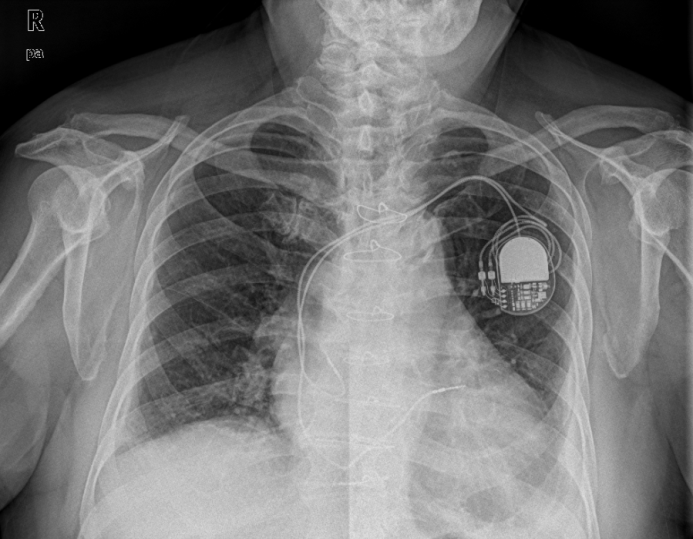

心脏起搏器则五花八门,目前常见的还是植入埋藏式起搏器。治疗范围也从最基本的缓慢心律失常延伸至快速室性心律失常和伴有QRS波增宽的慢性充血性心律失常,从使用时间可以分为临时心脏起搏器(经皮起搏、经静脉起搏、经食管心脏起搏、经胸心脏起搏)、永久起搏器,从起搏心腔可以分为单腔、双腔、三腔、乃至四腔心脏起搏器,从特殊用途可以分为频率应答起搏器、抗心动过速起搏器、埋藏式心脏复律除颤器(ICD),此外还有无导线起搏器、靠自身心跳蓄能的心脏起搏器。

图3 起搏器植入后胸部正位片

部分起搏器能起到除颤器作用,但除颤器却难以模拟起搏器的功能,请大家再看到有人把“除颤器”称作“起搏器”的时候,能为普及医学知识做出自己的贡献。